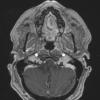

NEOPLASMS (GLIAL)

Astrocytoma, IDH-mutant, WHO Grade 2 (4)